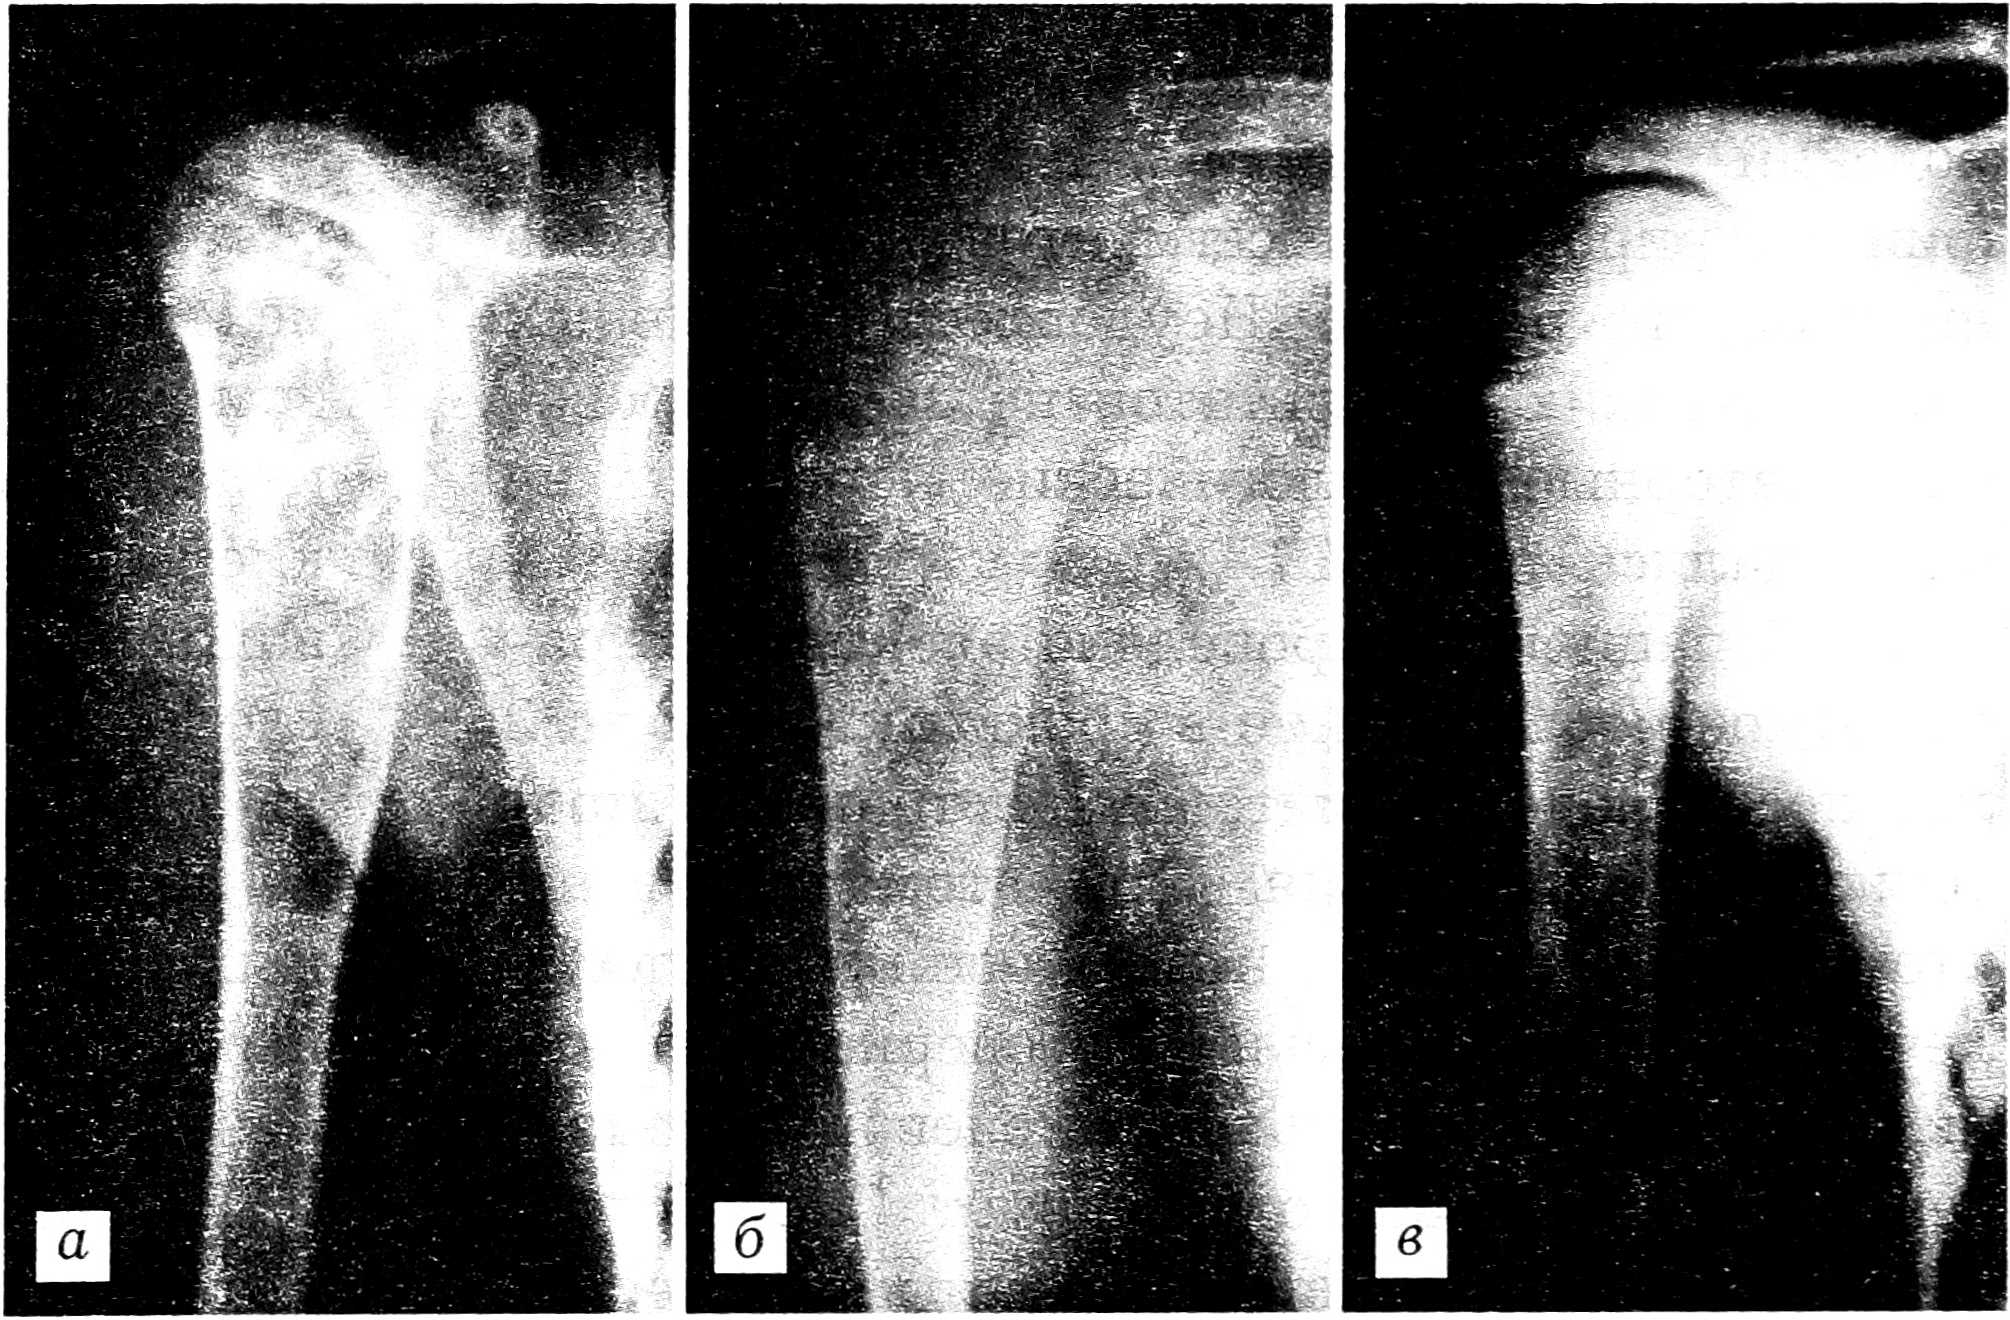

По предложенной методике лечились 34 пациента в возрасте от 4 до 16 лет: по поводу разного типа кист плечевой кости — 22 больных, бедренной кости — 6, большеберцовой — 3, малоберцовой, пяточной кости и ключицы — по одному больному. Положительные клинико-рентгенологические результаты достигнуты у 93% пациентов (см. рисунок). Укорочений, деформаций и мышечной гипотрофии оперированных сегментов не отмечено ни у одного ребенка. Неудовлетворительных косметических результатов не зафиксировано. Повторные патологические переломы не наблюдались.

Рис. 1. Рентгенограммы больного с солитарной кистой в верхней трети плечевой кости.

a — до лечения: киста в фазе остеолиза; б — через 3 мес после лечения методом проточного дренирования: видны явные признаки остеорепарации; в — через 10 мес после лечения: полное восстановление костной структуры.